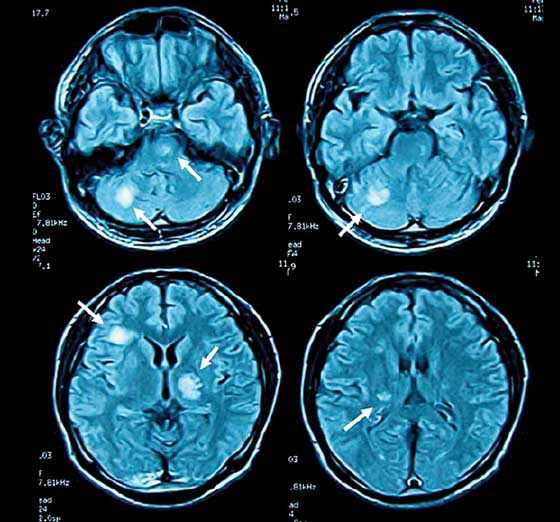

Sin embargo, el Dr. Erdem, en un estudio realizado a 113 buzos militares de Turquía, comparados con 65 no buzos, encontró lesiones en la sustancia blanca del cerebro (evidenciadas por RNM) en el 23% de los buzos frente al 11% del grupo control.

Estos hallazgos generaron mucha controversia, ya que hay diferentes estudios a favor y en contra de las lesiones del sistema nervioso central producidas a largo plazo por el buceo.

Tetzlaff y colaboradores, por su parte, demostraron que buzos comerciales de edad avanzada sin antecedentes de enfermedad por descompresión están en riesgo de presentar efectos perjudiciales en el sistema nervioso central, a largo plazo. Esto se asocia directamente con un deterioro de la actividad neuropsicológica con el aumento de la prevalencia de lesiones de la sustancia blanca del cerebro.